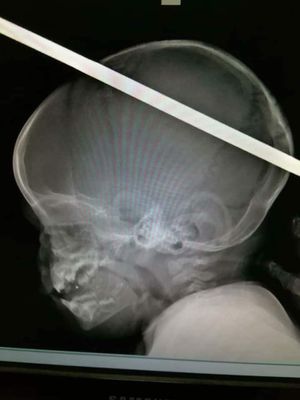

Child 3 year had came to emergency room at Cairo University of egypt for Neurosurgery after this accident fall down from 3 floor, and the operation was successful. Condition is stabilised.